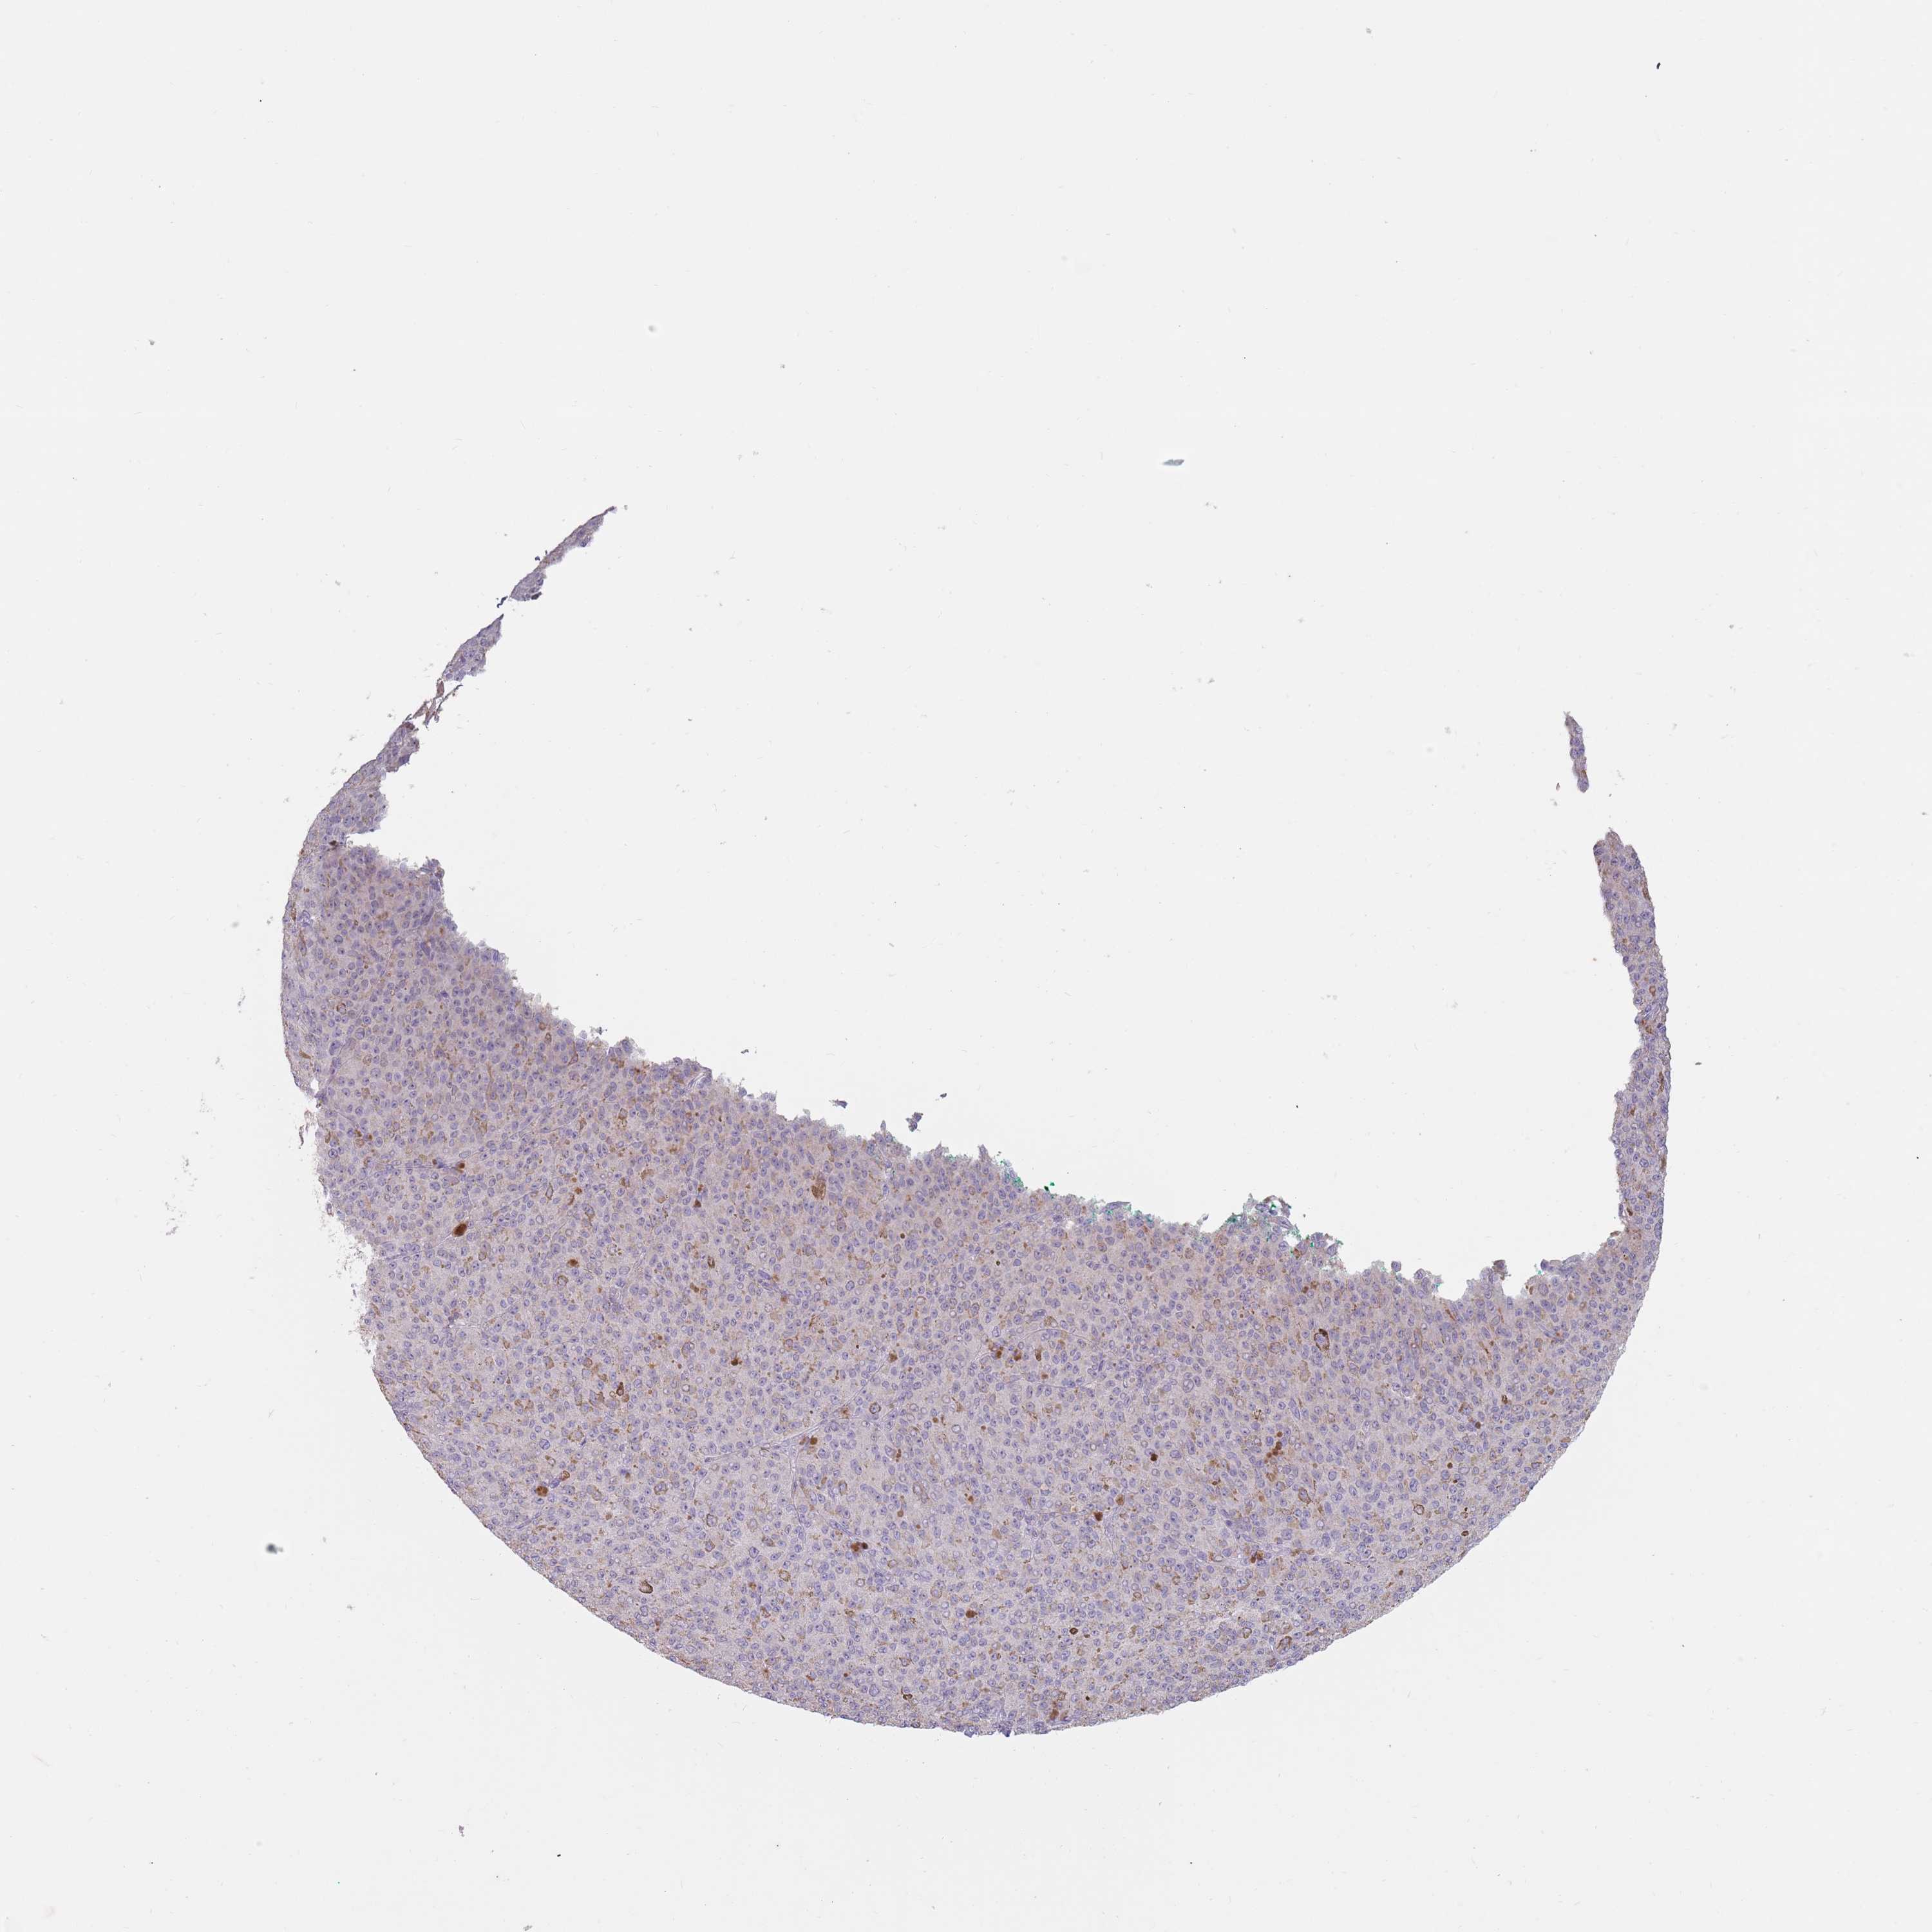

MELANOMA - Protein expressioni

A mouse-over function shows sample information and annotation data. Click on an image to view it in a full screen mode. Samples can be filtered based on level of antibody staining by selecting one or several of the following categories: high, medium, low and not detected. The assay and annotation is described here.

Note that samples used for immunohistochemistry by the Human Protein Atlas do not correspond to samples in the TCGA dataset.

Antibody stainingi

Antibody staining in the annotated cell types in the current human tissue is reported as not detected, low, medium, or high, based on conventional immunohistochemistry profiling in selected tissues. This score is based on the combination of the staining intensity and fraction of stained cells.

Each image is clickable and will lead to virtual microscopy that enables deeper exploration of all samples and also displays staining intensity scores, fraction scores and subcellular localization as well as patient and tissue information for each sample.

Antibody HPA046708

Staining

High

Medium

Low

Not detected

Intensity

Strong

Moderate

Weak

Negative

Quantity

>75%

75%-25%

<25%

None

Location

Nuclear

Cytoplasmic/membranous

Cytoplasmic/membranous,nuclear

Malignant melanoma, NOS

Malignant melanoma, Metastatic site